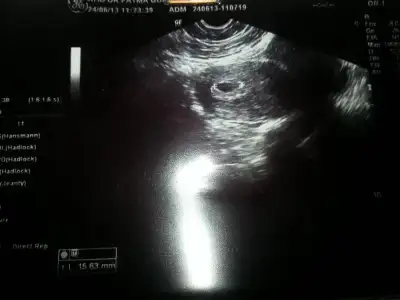

Kızlarrrrr bebegimmm :16::16::16::16::16::16::16::16::16:

• $20130627_151054.webp